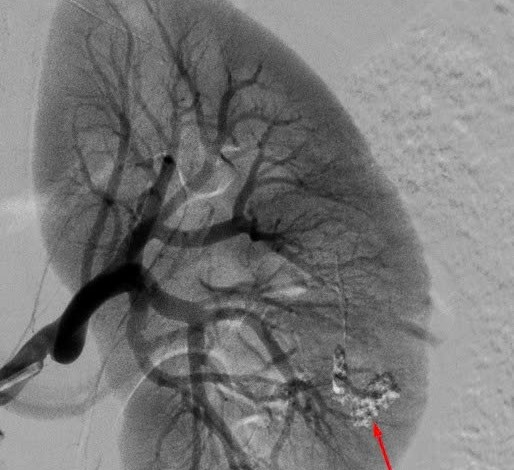

Through clinical examination, doctors recorded that the patient's abdomen was soft but swollen, pressing on the lower abdomen was painful, with clear abdominal wall reactions. Ultrasound results showed that there was a lot of free fluid in the abdominal cavity, no fetal sac was detected in the uterine cavity; beta-HCG test was positive. Based on clinical and paraclinical signs, doctors diagnosed the patient with ruptured right uterine eclampsia, abdominal hemorrhage.

Faced with critical condition, the patient was indicated for emergency laparoscopic surgery immediately. During the surgery, the team proceeded to remove the uterine uterine lump, and at the same time stopped bleeding in time to limit blood loss for the patient. After about 40 minutes, the surgery was completed. The total amount of blood lost by the patient is estimated at about 700 ml. Thanks to being treated quickly and according to the protocol, the patient survived the danger.